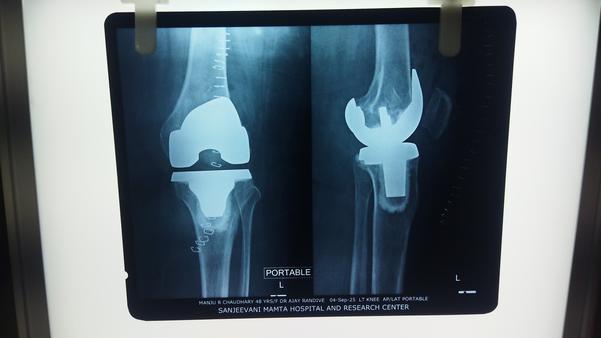

Dr Ajay Randive : IS MS Ortho (Mumbai) MRCSI ( UK) Consultant knee, Hip ,& Spine Surgeon, Dr Ajay Randhive is a eminent Knee, Hip , & Spine Surgeon practicing in to areas Andheri East,Santacruz East. Dr Ajay Randive did his MS Ortho residency from LTMMC, Sion Hospital Mumbai. He did overseas training in UK from 2003 till 2008. He is trained in total Knee Replacement, Hip Replacement, Revision Hip Replacement And Revision Knee Replacement Surgeries. He has worked at The Royal London Hospital. IN London where he worked a clinical fellow in joint Replacement unit. He has carried out more than 5000 Knee Replacement surgeries, 2500 Hip Replacement Surgeries, More Than 500 Revison Knee And Hip Replacement Surgeries 600 Spine surgeries & more than 1500 arthroscopic surgeries (Knee & Shoulder).